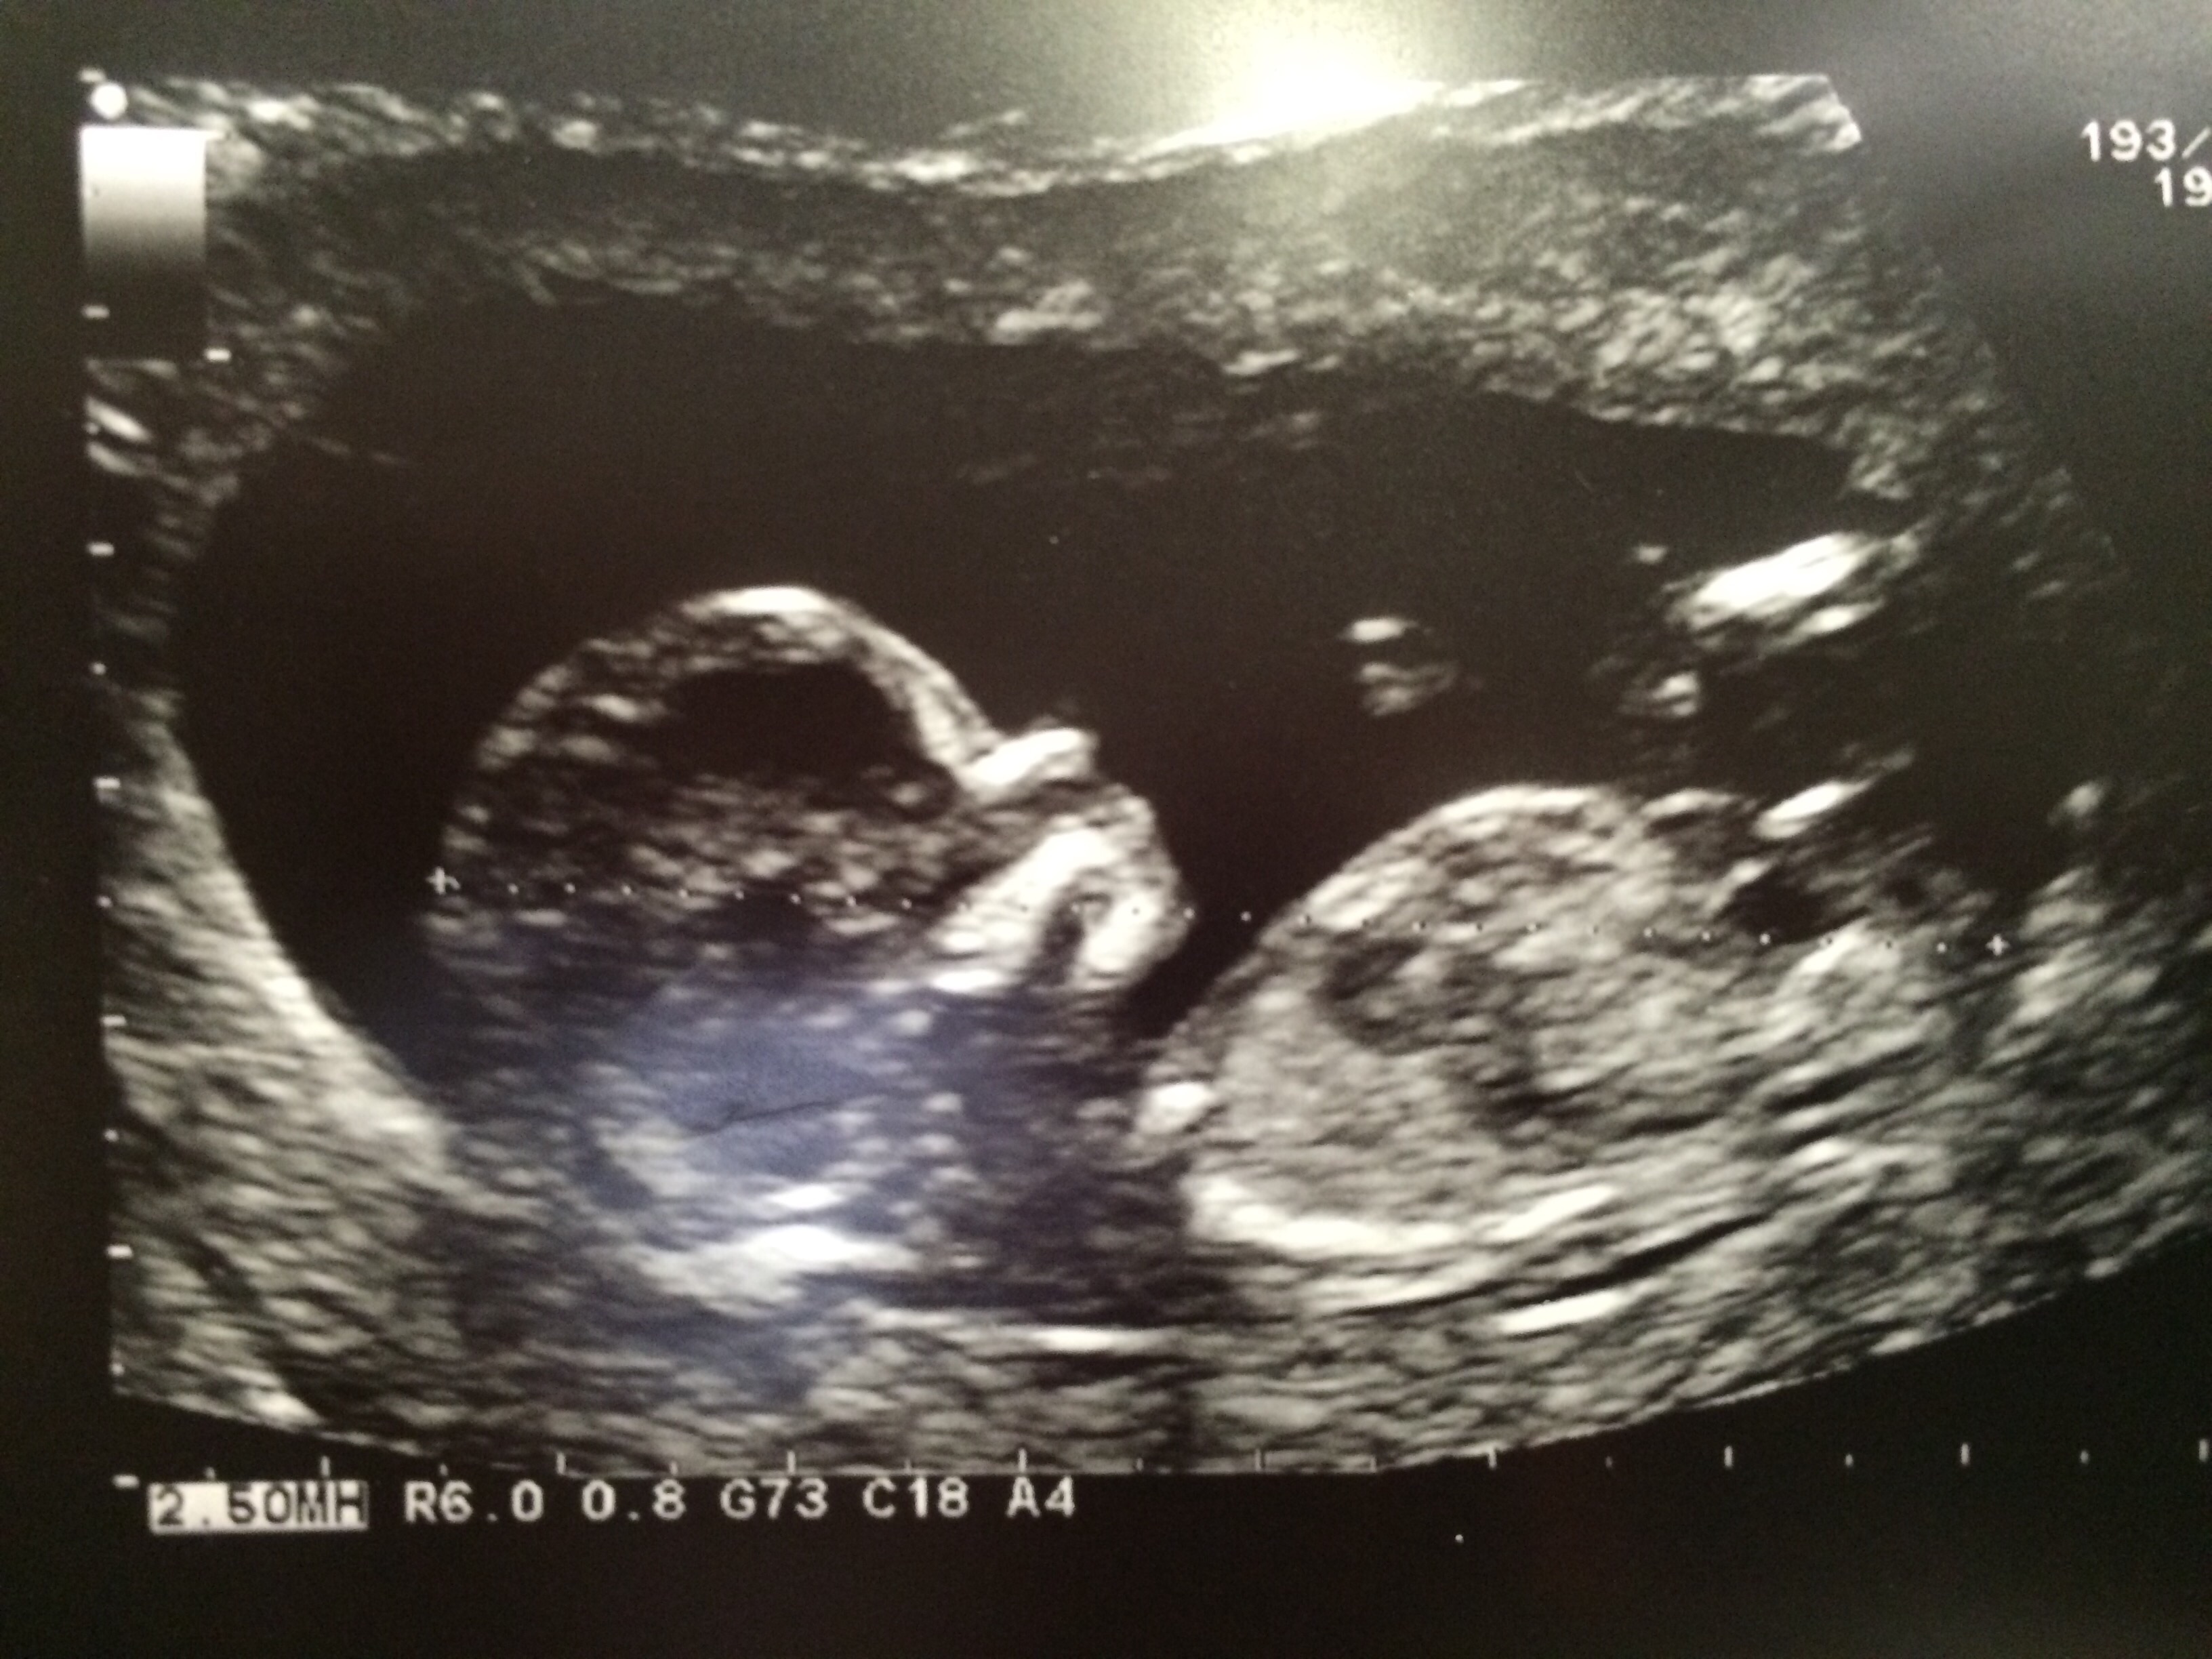

These were taken 13 weeks exactly.

Tricky because of baby's positioning but I would give tentative boy lean from second pic, seems like there is an angle there.

Maybe boy? But not the right angle, babe is turned towards us.

I don't see a nub but skull looks boyish

Think there is nub in 2nd pic. Xx

This is a boy! X